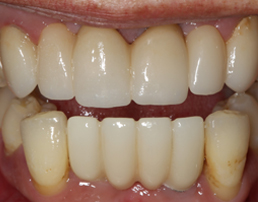

CROWN FITTED

Card image Actual Practice Photographs ©Dr.Pavan Bopanna